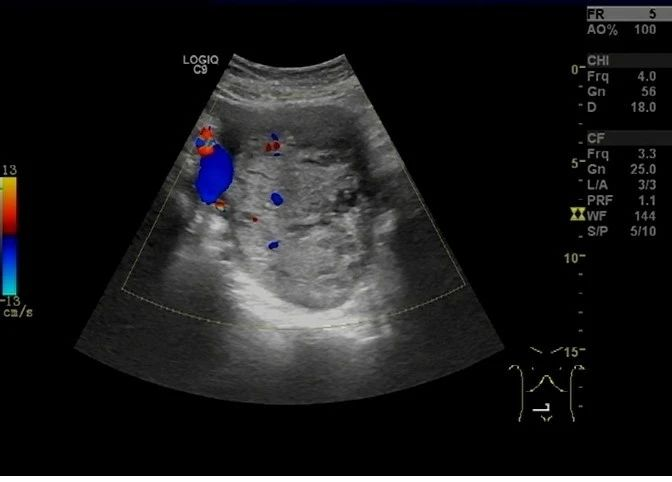

超声于右侧附件区见一囊实性团块,大小约 138 × 98 × 77 mm ,边界清,形态规则,内部回声不均,以实性为主(图 5), CDFI 于实性部分见少许血流信号(图 6), PW 测及低阻动脉血流频谱, RI:0.30 (图 7)。

图 6 CDFI 于实性部分见少许血流信号